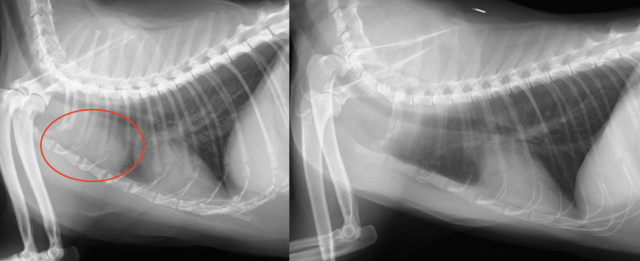

・レントゲン検査:大きさ、巨大食道症、肺炎、胸水貯留、遠隔転移(肺など)の評価

胸腺腫のレントゲン(左の赤丸、右は正常なレントゲン)